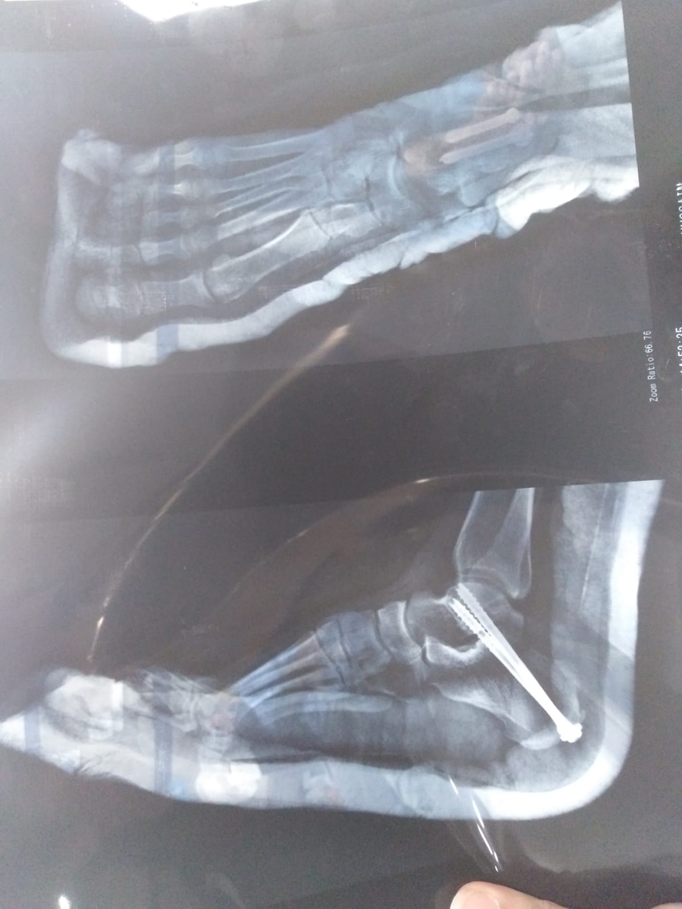

On his first post-op day, a 26-year-old football player presented to the IPD. The patient had a complete, close fracture of the talus bone, which was surgically repaired by the procedure of subtalar joint fusion. There were no pre-op or post-op complications. Patient had a history of foot injury in 2019, which was conservatively managed, but this did not heal his fracture, and he re-injured his foot by that time. Despite the fact that the patient was young and a non-smoker, the only reason for the non-healing of his fracture by conservative means was his early return to sports. The AROM of the associated joints of the lower limb was within functional range prior to surgery, but ankle ROM was limited due to fracture. After the surgery, the AROM of the ankle was not testable due to the cast.